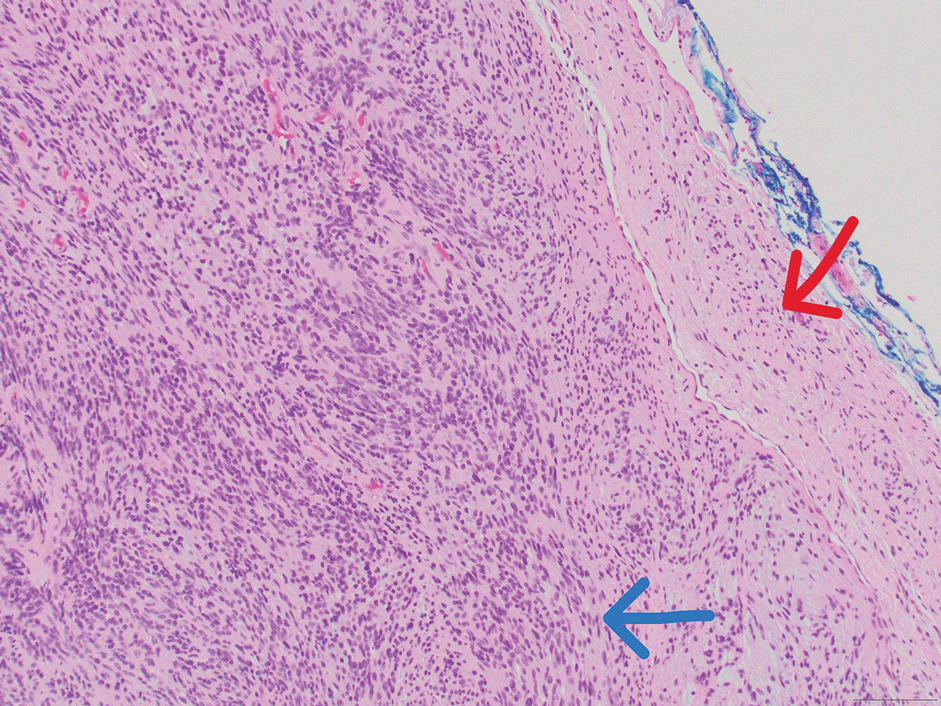

Microscopically, there was a superficial to deep dermal proliferation of tapered spindle cells in fascicles that were well circumscribed in nodules throughout the dermis with pale background stroma, mild mucin, and a thin capsule. The tapered spindle cells stained positive for SOX-10 and negative for Melan-A (Figure 1A). Staining for epithelial membrane antigen highlighted delicate cells around the periphery of the nodules, consistent with perineurium (Figure 1B). A diagnosis of plexiform palisaded encapsulated neuroma was made. No additional treatment was pursued due to the benign nature of the condition.

FIGURE 1. A, Plexiform palisaded encapsulated neuroma demonstrating fascicles of tapered spindle cells that stained positive for SOX-10 (original magnification ×100). B, Epithelial membrane antigen highlighted delicate cells around the periphery of the fascicles, consistent with perineurium (original magnification ×100).